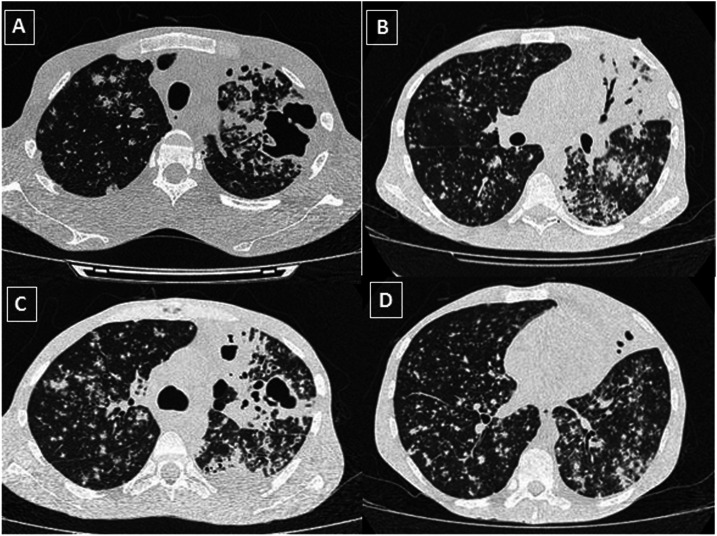

A 39-year-old Italian man who had been living in Brazil for more than 20 years arrived at the emergency department (ED) in April 2020 with a known diagnosis of HIV/AIDS (HIV viral load 293,313 copies/mm3 and CD4 cell count 145/mm3) and a 7-day history of sudden fever (temperature 38.0°C), myalgia, headache, and cough. He had poor adherence to antiretroviral therapy and previous use of marijuana and crack. He denied recent travel. He also tested positive for the surface antigen of the hepatitis B virus. He reported previous tuberculosis (TB) treatment for 3 months, although he did not complete the scheme. On physical examination, he was cachectic (weight 38 kg), with mild respiratory distress, a heart rate of 108 bpm, a respiratory rate of 18 rpm, and blood oxygen saturation (SPO2) levels of 93% without supplementary oxygen. No lymphadenopathy was observed. A chest examination revealed bilateral crepitations, rhonchi, and wheezes. Chest computed tomography (CT) revealed a large cavitation located in the left lung associated with bilateral glass-ground opacities (Figure 1A–D). Blood cell count presented low hemoglobin (5.4 g/dL) and hematocrit levels (16.5%), lymphopenia (408/mm3), and normal platelet and white cell count ranges. The C-reactive protein level was markedly elevated (118.8 mg/L). Hepatic and renal functions were normal. D-dimer, troponin, aspartate transaminase (AST), alanine transminase (ALT), and ferritin levels were at normal range. Acid-fast bacilli smears were positive, and MTB DNA was detected using PCR (GeneXpert MTB/rifampicin [RIF] assay) without RIF resistance. During hospitalization, the patient experienced respiratory distress and required continuous oxygen via nasal cannula 2 L/minute during the first 3 days. Admission to the intensive care unit and invasive mechanical ventilation was not required. Treatment with isoniazid, ethambutol, pyrazinamide, and RIF was initiated. He was also treated with azithromycin (500 mg/day), hydroxychloroquine (HCQ) (400 mg/day) for 5 days, and ceftriaxone (2 g/day). Antiretroviral therapy was not started to avoid complications with anti-TB treatment. After being hospitalized for 3 weeks, the patient was clinically stable and discharged to home with outpatient follow-up. Antiretroviral therapy was planned to be initiated after the first 8 weeks of anti-TB treatment.8

Figure 1.

Chest computed tomography (CT). (A–C) Axial thin-section unenhanced CT image revealing a large cavitation with air bronchograms and consolidation. (B–D) Axial thin-section unenhanced CT image showing randomly distributed (miliary) nodules in both lungs associated with glass-ground opacities and consolidation in the left lower lobe.